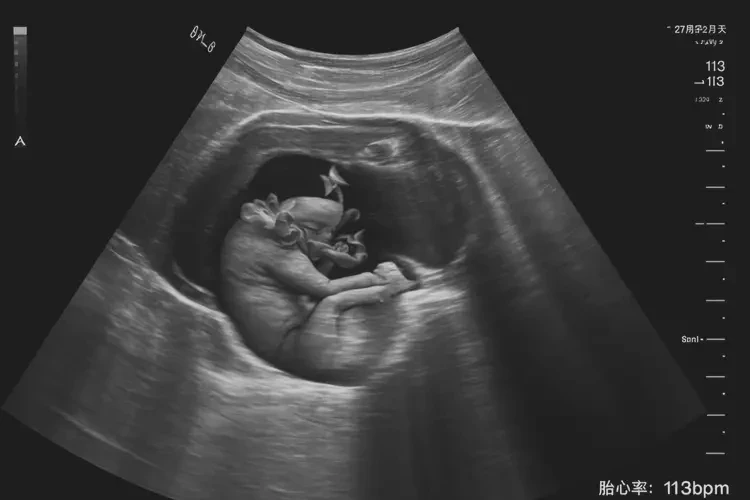

胎心113次/分钟在孕27周2天属于偏低范围。

胎心率是指胎儿心脏每分钟跳动的次数,正常情况下,胎心率在120-160次/分钟之间。在孕27周2天时,胎心率为113次/分钟,低于正常范围的下限,可能存在一些潜在问题。以下是对这一情况的详细分析:

胎心率113次/分钟在孕27周2天属于偏低范围,可能存在一些潜在问题。如果发现胎心率偏低,应及时就医,接受医生的评估和指导,以确保胎儿的健康和安全。